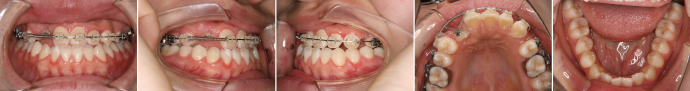

| 主訴 | 前歯の隙間が気になる |

| 年齢・性別 | 42歳 / 女性 |

| 治療方針 | 咬合力により上顎前歯が前方に傾斜したと思われるケース。元に戻りやすいため過蓋咬合をしっかり治して、保定には固定式のリテーナーも併用する。 |

| 抜歯部位 | 非抜歯 |

| 使用装置 | マルチブラケット装置 |

| 治療期間 | 16か月 |

| リテーナー | 上顎インビジブル、フィックス、下顎インビジブル |

| 費用 | 765,000円(税別) |